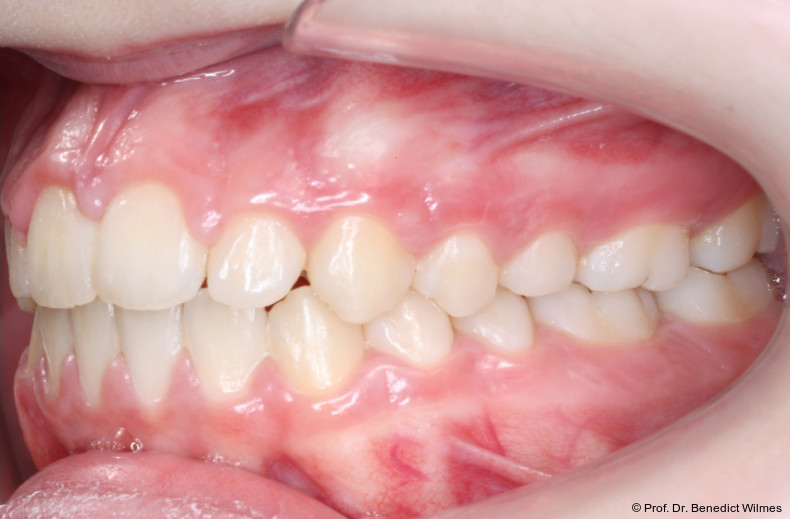

Eine 13-jährige Patientin stellte sich mit beidseitigem Kreuzbiss, einem anterioren offenen Biss und einer Angle Klasse II vor. Das viszerale Schluckmuster wurde mittels logopädischer Maßnahmen umgestellt, der offene Biss persistierte jedoch (Abb. 3a–l).